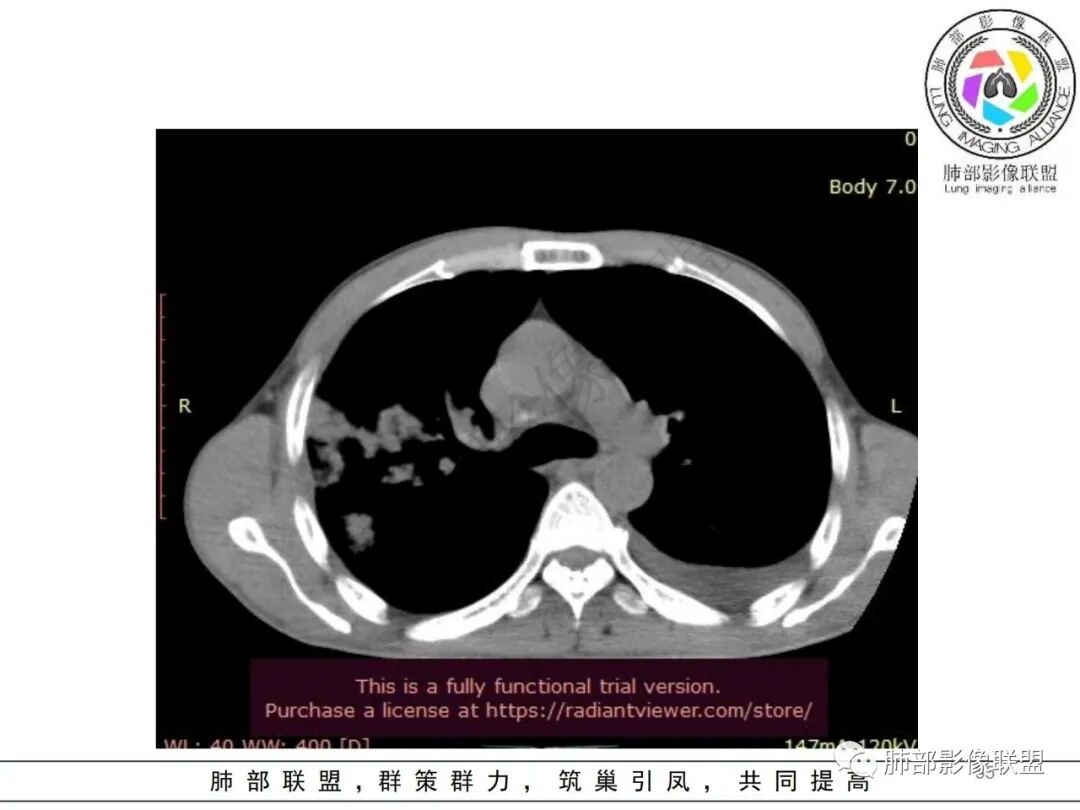

双肺多发大小不等结节影,边缘伴有磨玻璃影,边界欠清,部分与血管束相连,支气管似有穿行病灶内,结节有融合,左肺下叶厚壁空洞,伴有反晕征,左侧胸水,临床中年男性,发热40℃,CRP增高,感染性病变,1:类鼻疽伯克霍尔德菌(好发海南,影像表现也符合)

影像:双肺多发结节、实变影,大部分病灶边界不清,分布相对随机,左下肺坏死空洞形成,伴左侧胸水。

影像表现:双肺弥漫分布斑片影、实变影、磨玻璃影、结节影,晕征、反晕征,随机分布,部分病灶空洞形成前兆,左侧胸腔积液。

影像表现:双肺多发结节、实变影,大部分病灶边界不清,随机分布趋势,左下肺“反晕征”,似有形成空洞趋势。左侧胸腔积液。治疗后复查 ,大部分病灶吸收好转,呈较为典型血播分布,肝脏低密度块影,边界不清,符合肝脓肿。